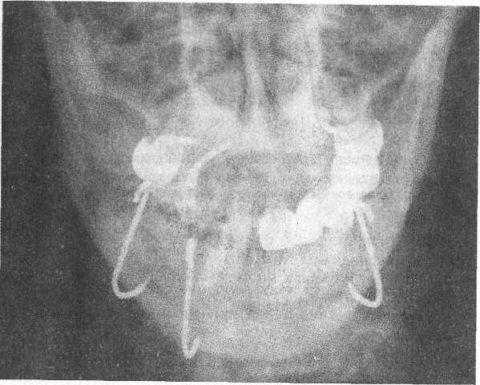

Диагноз: сочетанная деформация челюстей, асимметричная деформация по горизонтали. Планируется: остеотомия челюстей по Ле_Форт 1 и сагитальная нижней челюсти.